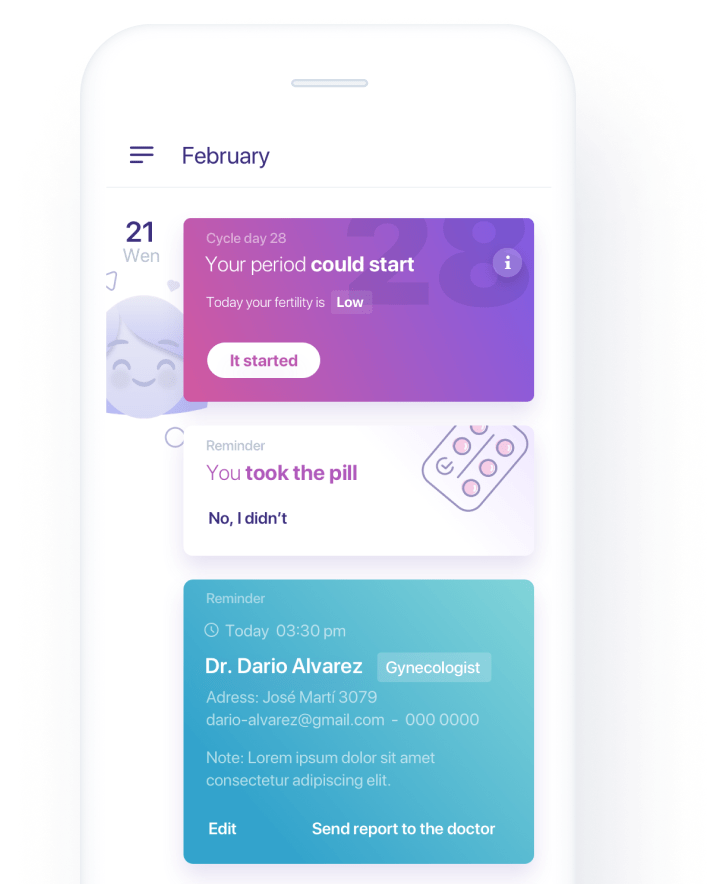

Healthcare

People-centric healthcare design and solutions, from virtual care, integrations, to smart devices.

We created an integrated breast health monitoring system, featuring a mapping device, an app with advanced dynamic AI algorithms and blockchain.

Healthcare Solutions